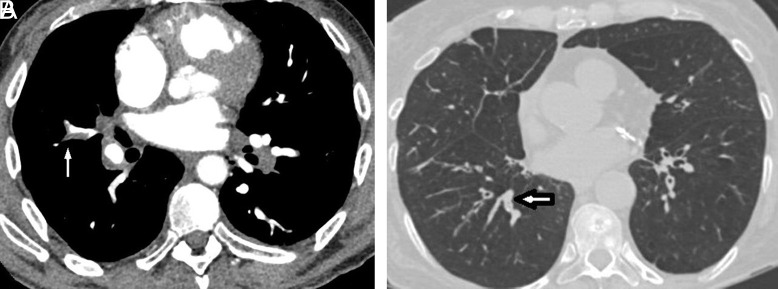

Material and methods: The retrospective study examined 200 participants diagnosed with both COPD and pulmonary embolism. Of these, 100 patients exhibited mucus plugs in the segmental and subsegmental branches of the pulmonary bronchial tree, while the remaining 100 did not, using computed tomography images for diagnosis. Data collection encompassed a comprehensive review of patient records, including medical history and imaging reports, to determine the presence of mucus plugs and the localization of clots in pulmonary embolism cases.

Results: Patients with mucus plugs exhibited a notably longer duration of COPD (P = .021) and a higher mean pulmonary arterial occlusion index (23 vs. 12, P = .001). Moreover, the prevalence of clots in major pulmonary arteries was significantly elevated in the mucus plug group compared to the non-mucus plug group (P < .05). Conversely, patients without mucus plugs displayed a higher incidence of clots in segmental and subsegmental arteries (P < .001). Strong positive correlations existed between mucus plugs in segmental branches and clots in major pulmonary arteries, with moderate to strong correlation coefficients (0.51 to 0.62, P < .05). Additionally, strong negative correlations were observed between mucus plugs in segmental branches and clots in segmental and subsegmental arteries, with correlation coefficients (CC) ranging from -0.74 to -0.76 (P < .05). Similarly, a significant negative correlation was noted between mucus plugs in subsegmental branches and clots in subsegmental arteries (CC: -0.68 and -0.71, P < .05).